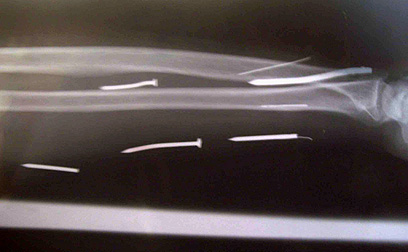

אזרחית סרי לנקה, ששבה לארצה אחרי שעבדה כעוזרת בית בסעודיה, חשפה מסכת עינויים מזעזעת שעברה בידי מעסיקה. ממשלתה הודיעה הלילה (יום ה') כי היא חוקרת חשד שהתוקף החדיר 24 מסמרים לגופה בתור עונש "חינוכי".

ל"ט אריוואתי (49) נסעה לסעודיה במרס בתקווה להרוויח כסף בתור עובדת זרה על מנת לשוב בבוא היום לארצה. אולם לבסוף היא החליטה לשוב בשבוע שעבר בגלל ההתעללות שחוותה במקום עבודתה. בבדיקה רפואית שנערכה לה התגלו 24 מסמרים, חלקם באורך חמישה סנטימטרים, שננעצו בידיה וברגליה.

צילום רנטגן של אחת מזרועותיה של האשה (צילום: AFP)